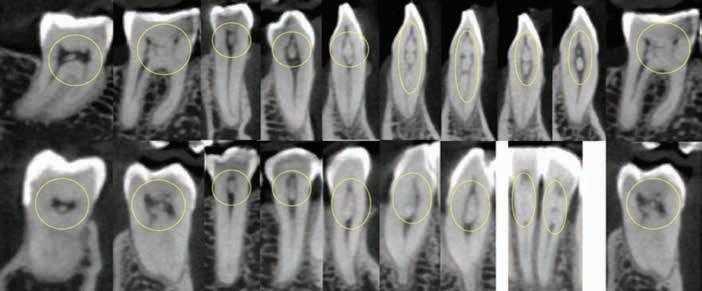

Her full mouth intraoral radiographs revealed generalized pulpal calcifications of various dimensions in the pulp chambers and root canals. In at least one tooth, multiple discrete pulpal calcifications were observed. All teeth with existing pulpal calcifications were asymptomatic, and did not show any radiographic signs of periapical bone loss or periodontal ligament (PDL) widening.

Figure 1. Full mouth radiographic survey reveals multiple pulpal calcifications of various dimensions affecting the pulp chamber and radicular pulp of patient’s remaining dentition.

Figure 2. Full mouth radiographic survey reveals multiple pulpal calcifications of various dimensions affecting the pulp chamber and radicular pulp of patient’s remaining dentition. Multiple discrete pulpal calcifications can be noted on upper left first molar pulp chamber.

showing distinct pulp stones in canals of teeth #8, 9, 19, 23, 24,

4B. 8X8 CM MORITA ACCUITOMO 170 CONE BEAM CT SCAN—Sagittal and coronal view showing distinct pulp stones in canals of teeth #6, 7, 8, 9, 10, 11, 14. Multiple stones are noticed in the pulp chamber of 14.

Figure 4A. 8X8 CM MORITA ACCUITOMO 170 CONE BEAM CT SCAN—Axial view

25, 26, 27.

Figure

Figure 4C. 8X8 CM MORITA ACCUITOMO 170 CONE BEAM CT SCAN—Sagittal and coronal view showing distinct multiple pulp stones in canals of teeth #19, 22, 23, 24, 25, 26, 30. Single stones noticed in #27, 28, 31.